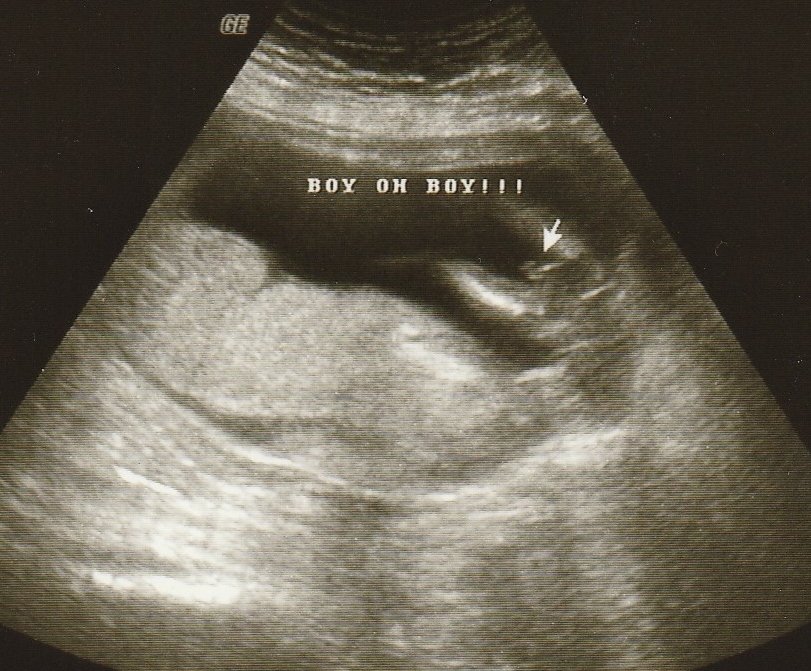

1 Attachment(s)

Attachment 22281

So they are saying it looks like a boy. I'm in shock.